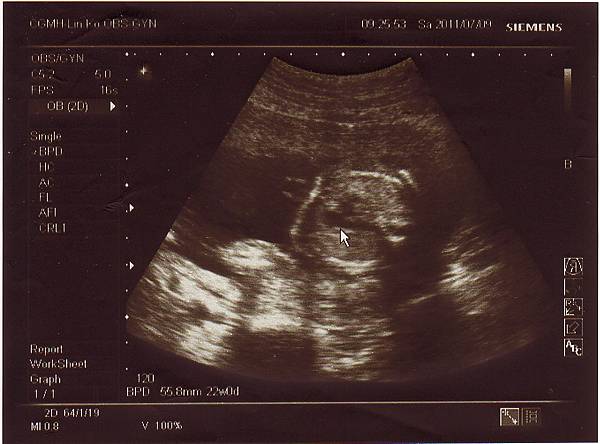

兩個星期後,也就是今天2011.07.09回診了,

還好一切順利,寶寶健健康康的,

醫生說是個長腿妹妹,心跳強而有力,

我懸了兩個星期的大石終於可以放下囉!